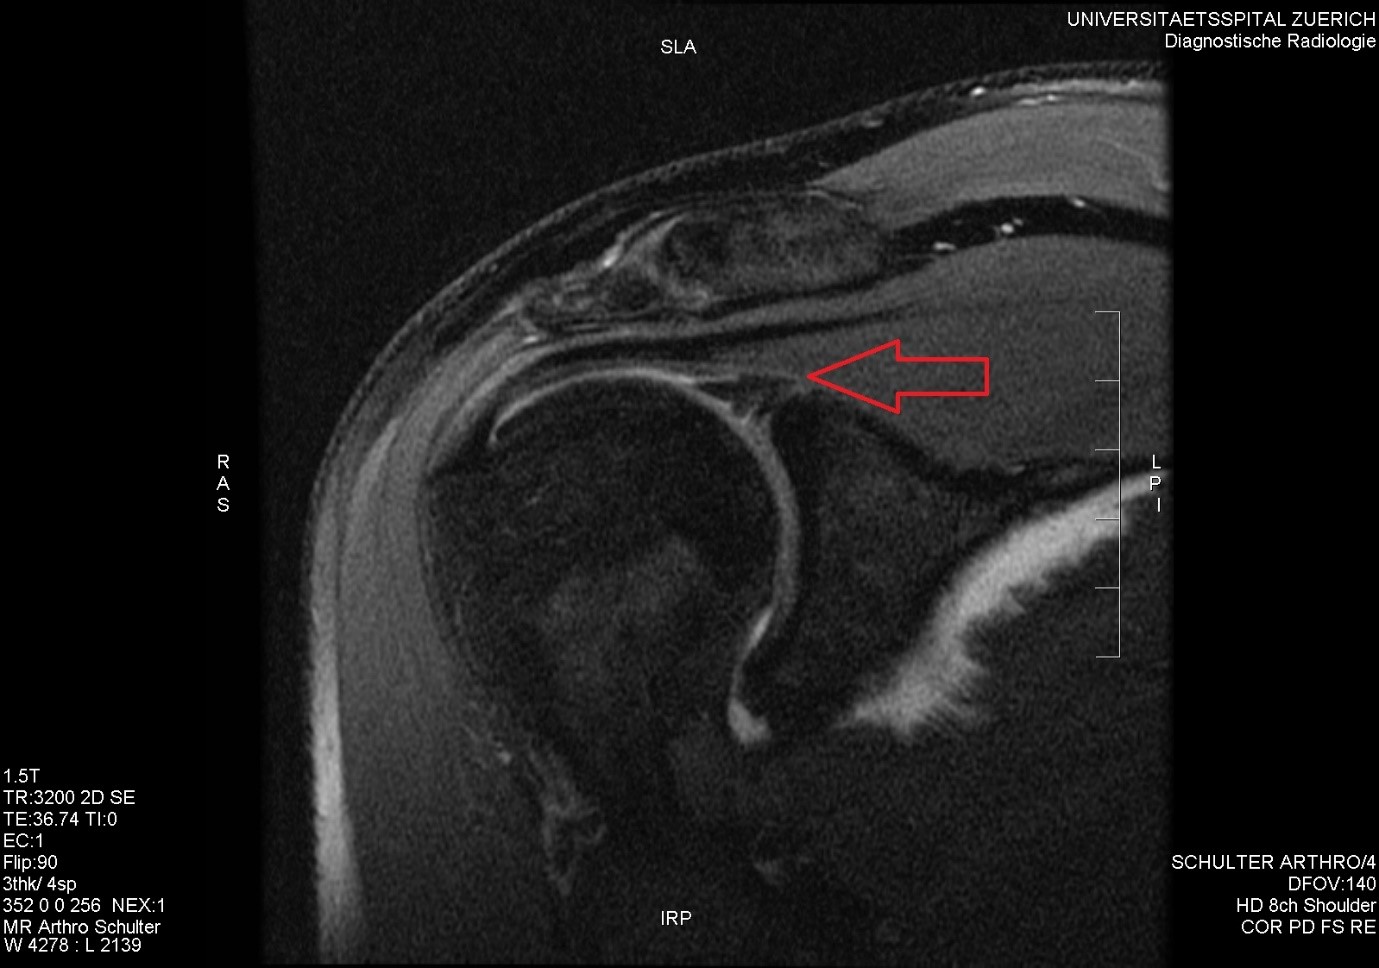

Labral Tears Dr Pant Sydney Shoulder Unit

From sydneyshoulderunit.com.au

Labral Tears Dr Pant Sydney Shoulder Unit Can You Still Run With A Labral Tear here’s what you should know about hip labral tears, plus exercises to get you running stronger and healthier than before. suffering a labral tear can be a setback for athletes and active individuals. here’s what you need to know about labral tears—the causes, symptoms, and treatment options—to get you on the. the idea is that if. Can You Still Run With A Labral Tear.